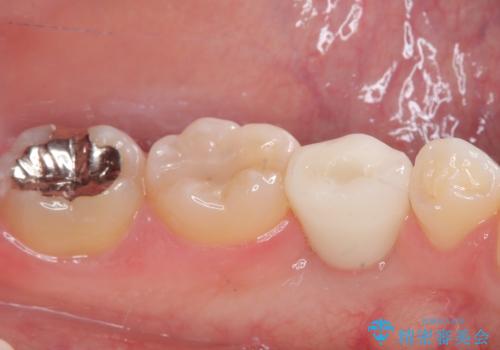

- 乳歯を抜歯したところにインプラントをしたいと来院された患者様です。

永久歯の先天欠如による乳歯の晩期残存があり、その乳歯が虫歯になってしまい保存不可能になり、他院で抜歯をし義歯を使用していた状態です。

義歯では嚙みづらいため、インプラントによる補綴をしていくこととしました。

義歯と違ってしっかり噛めるようになって食事がおいしくなったと満足していただけました。